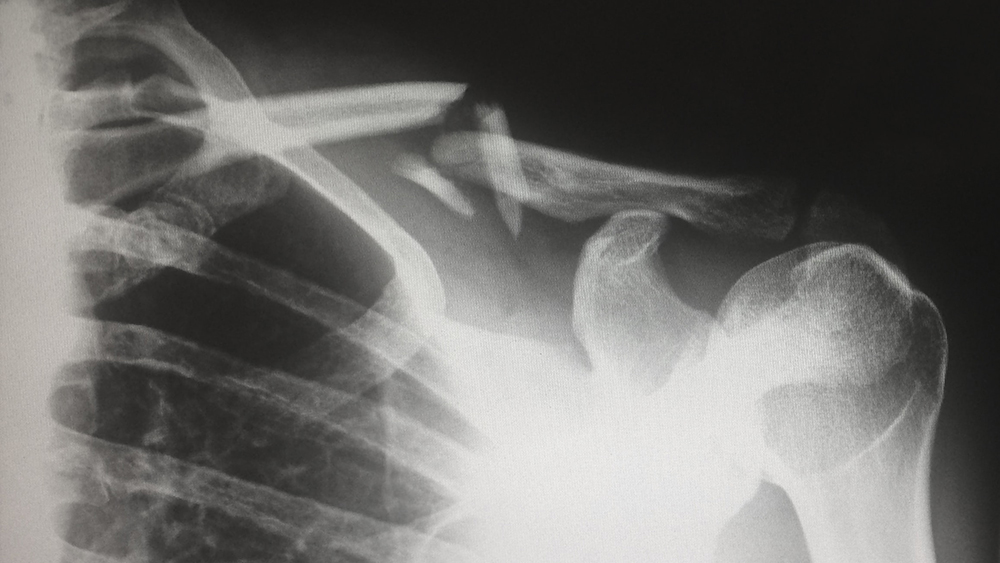

不(bù)僅“假期綜合症”多(duō)發,春節前後,骨病♠•φ₹發病者也(yě)不(bù)同程度的(de)增多(duō),不(b↑∑ù)少(shǎo)人(rén)出現(xiàn)頸椎腰椎痛、關節痛↔₹₩等症狀。

老(lǎo)年(nián)人(rén)手腳靈活性、協調性差,尤≥¶≥其是(shì)患有(yǒu)骨質疏松的(de)老(l¥☆↕ǎo)年(nián)人(rén),大(d©&≤Ωà)掃除期間(jiān)輕微(wēi)的(d ε₹e)碰撞和(hé)跌倒都(dōu)可(kě)能(φ£ néng)導緻骨折。這(zhè)些(xiē)≥≥↕×其實都(dōu)跟缺鈣有(yǒu)很(hě™<γn)大(dà)關系。